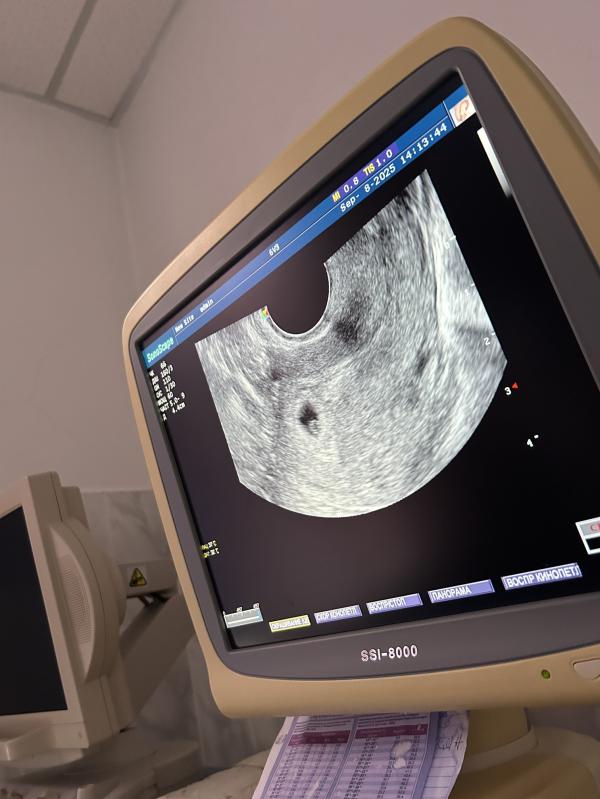

Первое узи неделю назад

И второе сегодня

@r_dinara_, эмбрион есть, они написали ктр 1,6

У вас на прошлом узи только плодное яйцо было, сейчас уже есть эмбрион с размером 1,6 мм 😀

Через пару недель может 2,5-3 можно будет посмотреть наличие сердцебиения 😀